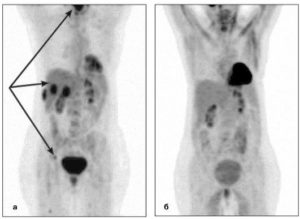

Результаты ПЭТ/КТ-исследования. Слева: неходжкинская лимфома (поражение левой небной миндалины и селезенки, поражение лимфоузлов выше диафрагмы. Справа: ходжкинская лимфома (поражение лимфоузлов по обе стороны от диафрагмы, с тенденцией к слиянию в массивные конгломераты, наиболее крупные в подмышечной области слева и в лимфоузлах средостения справа. III стадия)

На первой-второй стадии заболевания наблюдается ограниченное поражение лимфоузлов или одного экстралимфатического органа по одну сторону диафрагмы – мышечной перегородки между брюшной и грудной полостями. Как правило, самым первым симптомом лимфомы является увеличение лимфатических узлов. Биопсия пораженного лимфоузла и анализ на гистологию позволяют установить правильный диагноз.

На третьей-четвертой стадии выявляется поражение лимфоузлов по обе стороны от диафрагмы и/или нескольких экстралимфатических органов. Пациент жалуется на симптомы, характерные для большинства онкологических болезней: апатию, усталость, похудение, а также на симптомы, связанные с поражением конкретного органа.